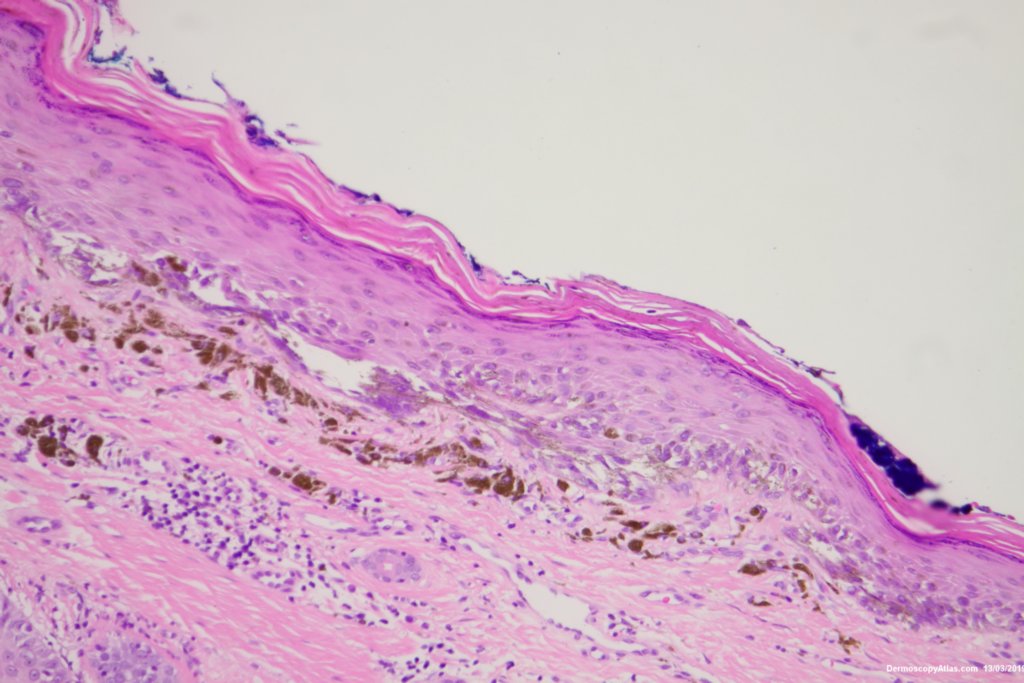

The histology was reported as an in situ melanoma with some dermal regression. It was excised with 5 mm clinical margins after the initial narrow excision biopsy.